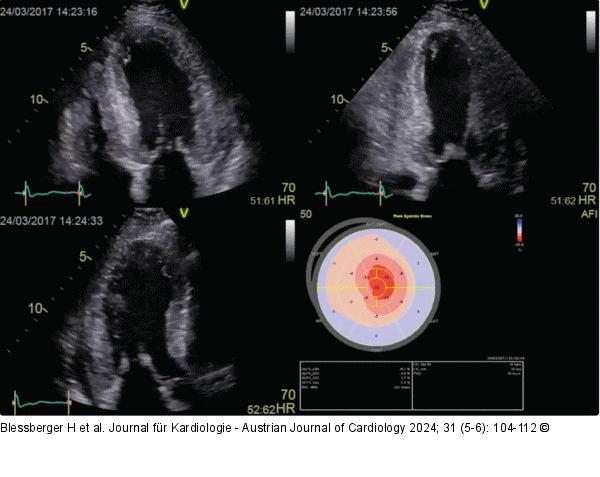

Abbildung 7: Echo Apikaler 4-, 2- und 3-Kammerblick und zugehörige Bull’s-Eye-Darstellung des linksventrikulären longitudinalen Strains: Das Muster mit erhaltener Kontraktilität am Apex und eingeschränkter Kontraktilität an der Basis und den mittleren Segmenten wird als „Cherry on top“-Muster bezeichnet und ist typisch für die kardiale Amyloidose. |

Apikaler 4-, 2- und 3-Kammerblick und zugehörige Bull’s-Eye-Darstellung des linksventrikulären longitudinalen Strains: Das Muster mit erhaltener Kontraktilität am Apex und eingeschränkter Kontraktilität an der Basis und den mittleren Segmenten wird als „Cherry on top“-Muster bezeichnet und ist typisch für die kardiale Amyloidose. |